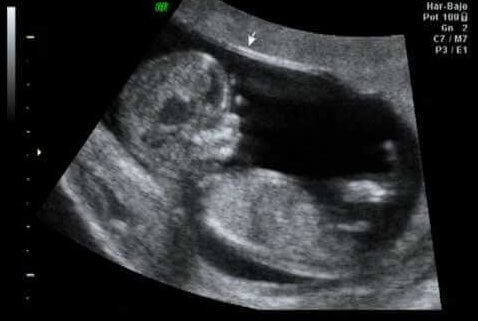

Ultrasound in week 12 of pregnancy

As a turning point of the first trimester, the 12th week can be an ideal time for the first ultrasound. This way we can verify that the organs are developing correctly. We can also check the baby’s size and weight, as well as the presence of the nuchal translucency, the liquid all fetuses have in the nape.

“This is a trascendental time, given that specialists claim that between 60 and 70% of malformations the fetus might present can already be detected at this point.”

On the other hand, the width of the fetus’s nape is measured, a figure that is part of the first trimester check-up, allowing us to detect the risk of an anomaly in the number of chromosomes (know as aneuploidy), especially trisomy 21 or Down syndrome. This is possible thanks to the relationship between these data and other studies, including:

- The mother’s age

- Hormonal values

- Nuchal translucency values

The exciting part, apart from noticing the fetus’s first activity, is the estimation of the due date for childbirth. In any case, and with no intention of raining on your parade, the date is accurate only 5% of times.